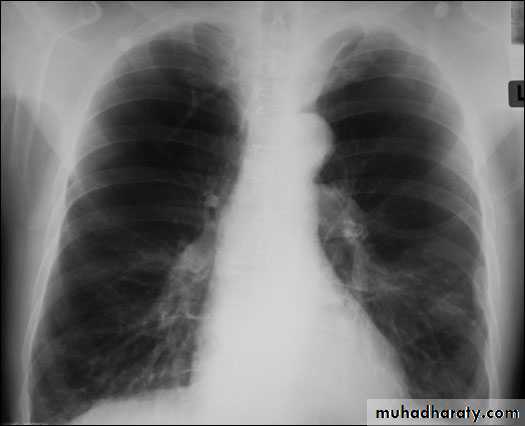

Radiology

Chest x-rayHyperlucency

Vascular attenuationHyperinflation (emphysema).

Chronic obstructive bronchitis